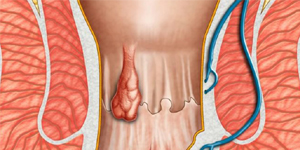

Sanjivani Ayurvedashram provides effective treatment for a whole host of ailments including sexual disorders of both males and females such as Erectile Dysfunction, Premature Ejaculation, Loss of Libido, Less and Unhealthy Sperms, Nightfall, Penis Enlargement, Spermatorrhea, Infertility, Lack of enjoyment during sexual intercourse, Vaginismus, Vaginal Dryness, Leucorrhea, Irregular Periods, Breast Enlargement, Vaginal Tightening. Other specialized medications and treatments available are for Diabetes, Leucoderma (Vitiligo), Obesity, Migraine, Arthritis, Hairfall, Kidney Disorder, Piles etc.